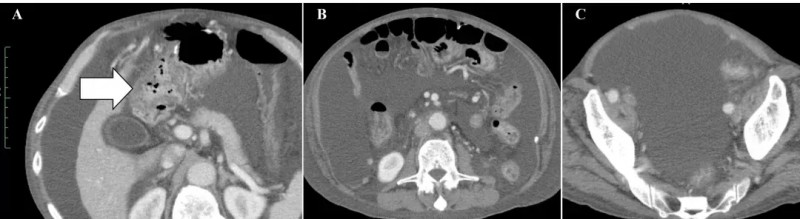

治疗前后变化显著:治疗前,腹部CT可见十二指肠周围大网膜明显扩张(详见下图A箭头所示),且存在大量恶性腹水(详见下图B、C)。

▲图源“Cureus”,版权归原作者所有,如无意中侵犯了知识产权,请联系我们删除